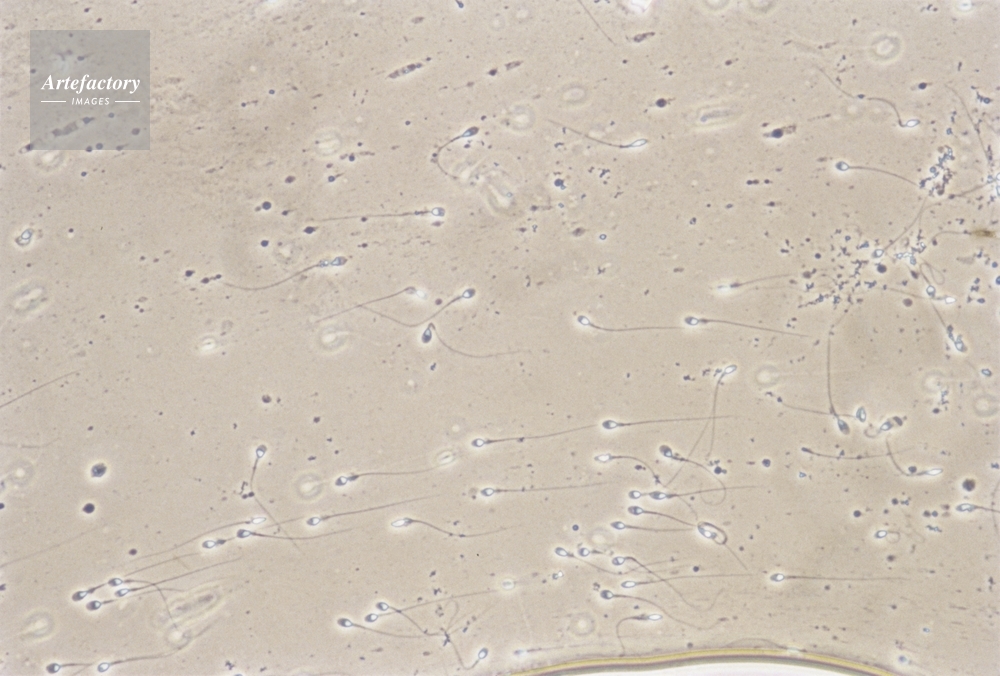

| 作品タイトル | 精子・ヒト | モデルリリース | なし | |

| キャプション | 倍率×100倍 | 制限事項 | ||